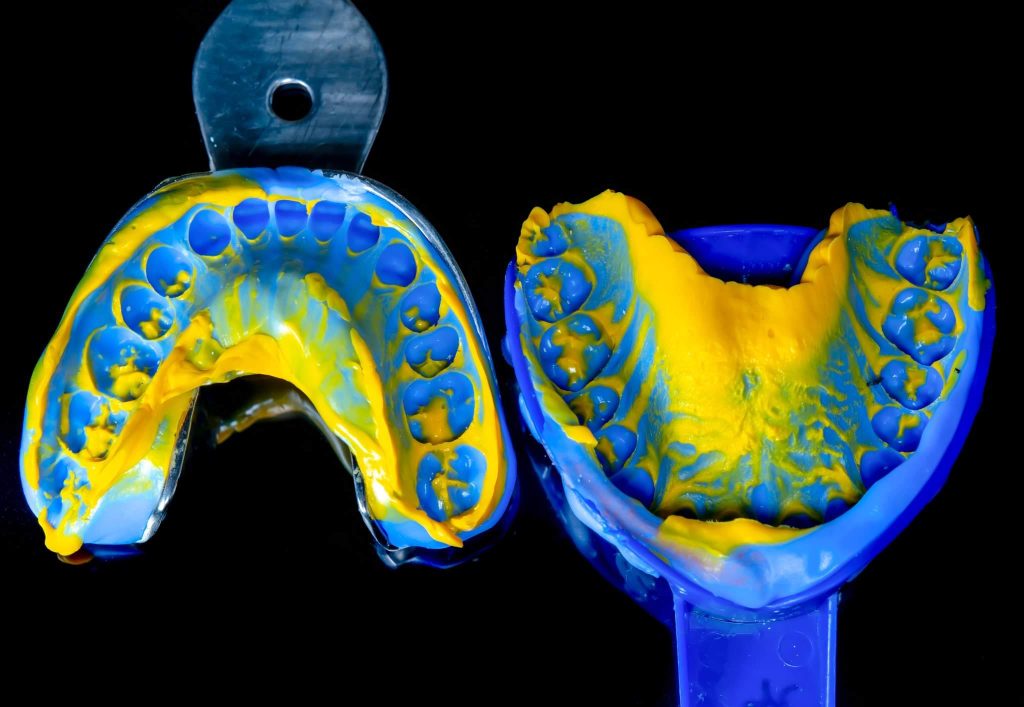

The case presented in this case report is for a 27-years-old female patient with a chief complaint of aesthetic correction for her smile. The patient was unhappy with her smile. After clinical examination, there were previous old composite veneering done poorly and incorrectly to close the multiple interdental spacing. After discussing the various treatment options (i.e., orthodontic treatment, direct, or indirect veneers), indirect ceramic veneering was selected. The step-by-step treatment protocol is presented in the images below.